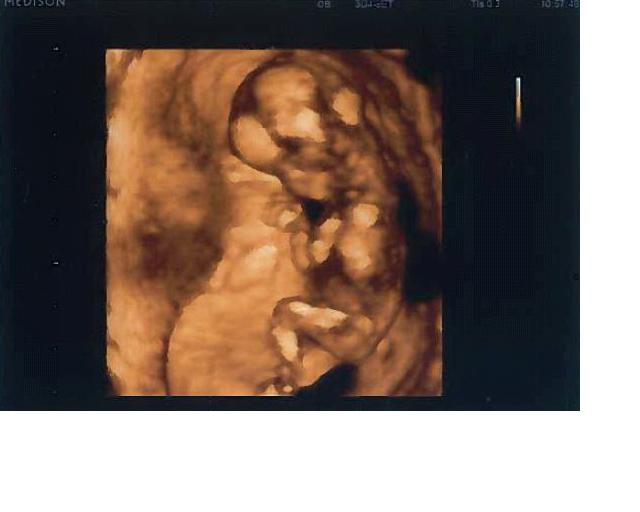

Ahoj kočičky, tak se hlásím po další kontrole včera. Bylo to krásný, hlavně ten 3D UZ, jsme zdraví, takže mě čeká za 14 dní ten tripletest a pak až v září další UZ, no moc se těším. Posílám fotečku, sice trochu nekvalitní, ale podstatné domyslíte

Už máme 12 cm, pašák

Nebo teda holčička? no já nevím pořád

teda já si myslím, že je to kluk, ale tak je to fuk